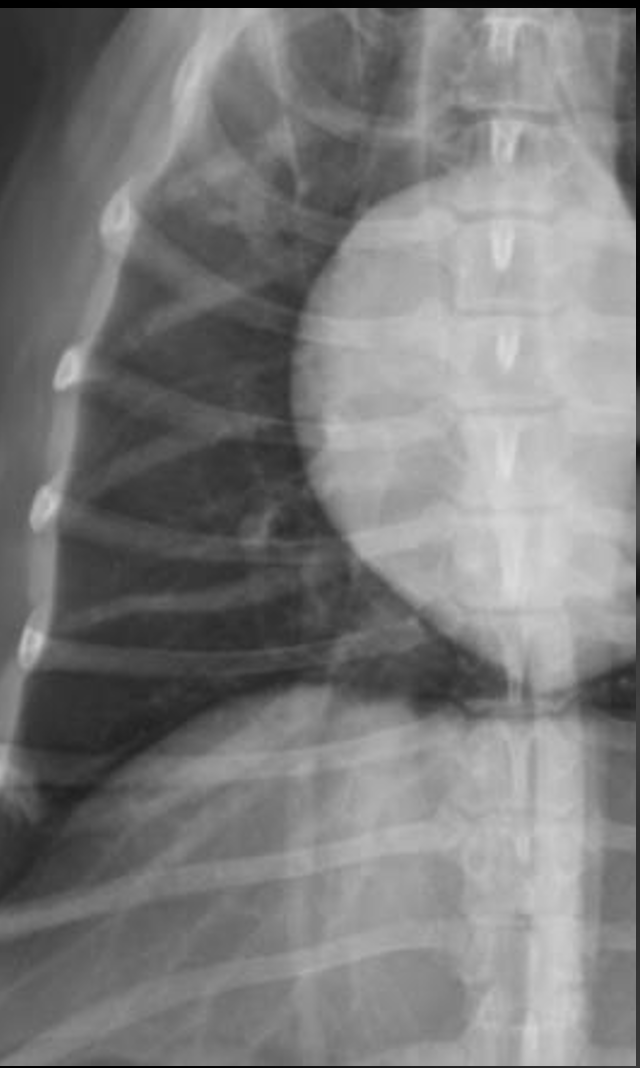

What is shown in these images?

generalized cardiomegaly